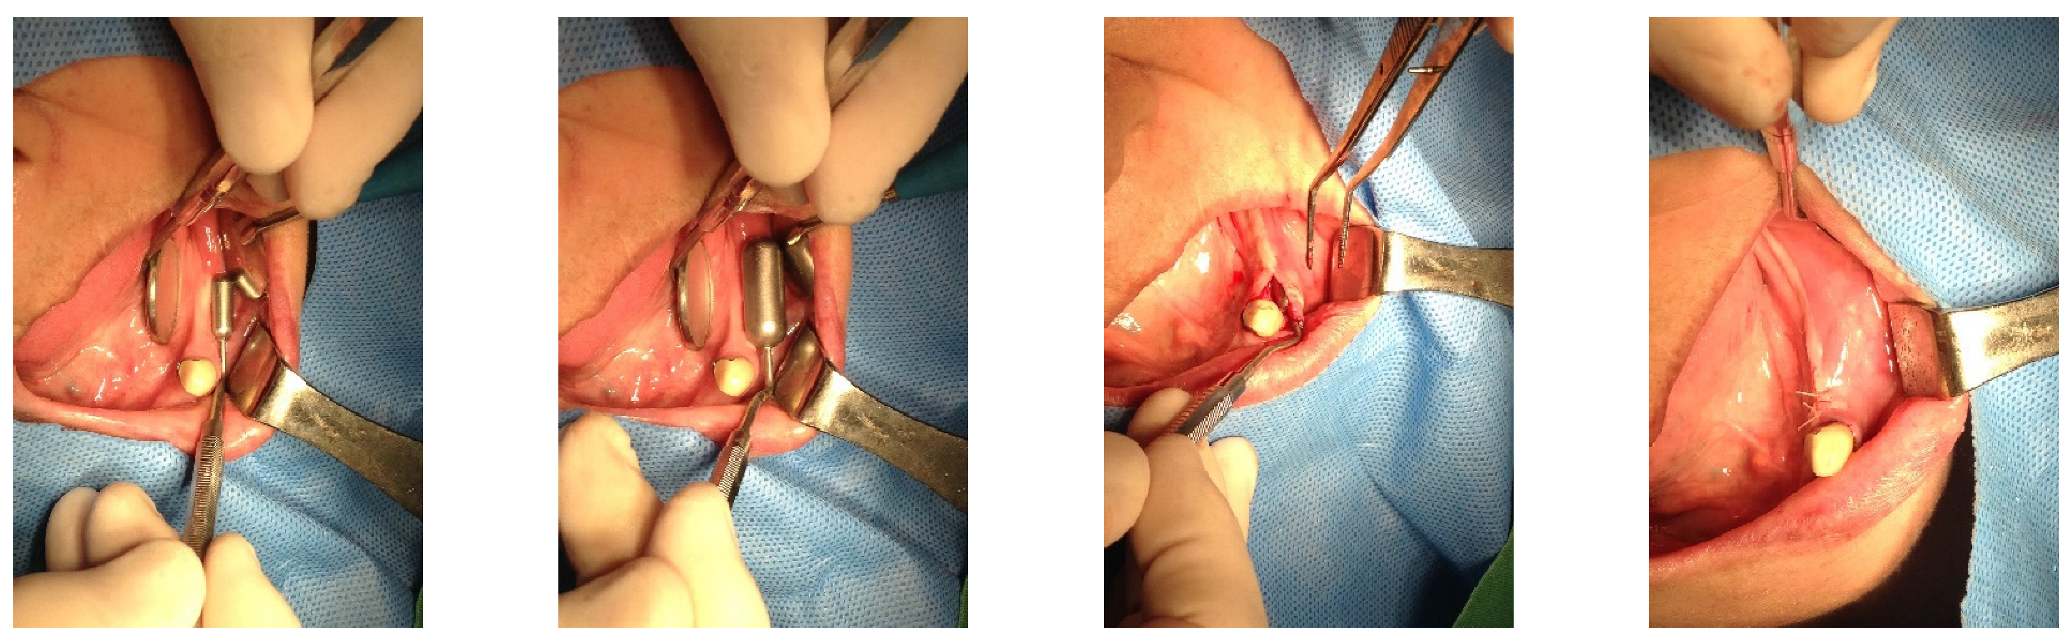

On 28 May 2015, a 1.3 mL SITE was inserted into the right edentulous ridge through a small pouch created by a 4 mm stab incision. On 2 June 2015, wound dehiscence occurred at the insertion site of the SITE on the right side, necessitating the removal of the SITE. Consequently, a new 0.7 mL SITE was inserted on 9 September 2015 (Figure 2).

Figure 2. On 28 May 2015, a small incision was made in the right posterior edentulous site of the mandible, through which a Self-Inflating Tissue Expander (SITE) was inserted into a subperiosteal pouch and subsequently sutured. On 2 June 2015, wound dehiscence occurred at the insertion site of the SITE on the right side, necessitating the removal of the SITE. Consequently, a new 0.7 mL SITE was inserted on 9 September 2015.